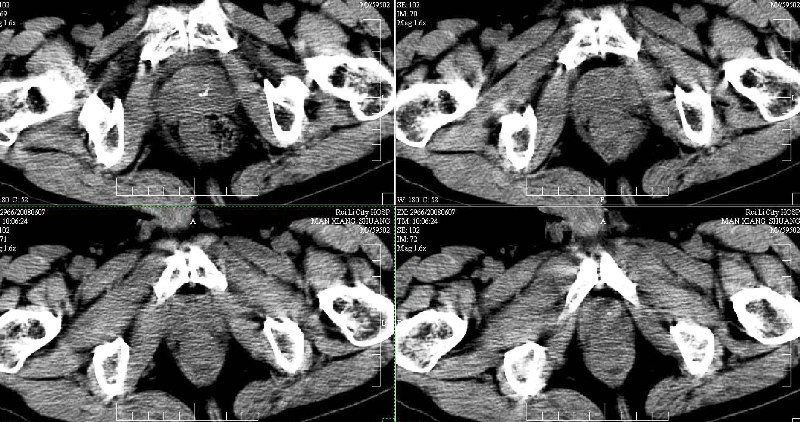

ct(椎间盘扫描):椎间盘炎,建议dr。

dr:l4骨质破坏,转移可能。

胸部摄片未见异常。临床医生体检发现上腹部饱满。

ct:肝癌腰椎转移。临床医生:肝脏、骨转移,肿瘤来自?前列腺?!

支持肝癌伴椎体转移瘤。腹膜后建议ct增强,好象有增大的淋巴结。

1、支持肝癌肝内及腰椎转移。

2、肝脏内好象有多个病灶,建议增强检查。

3、前列腺好象还可以,不过图像看得不太清。